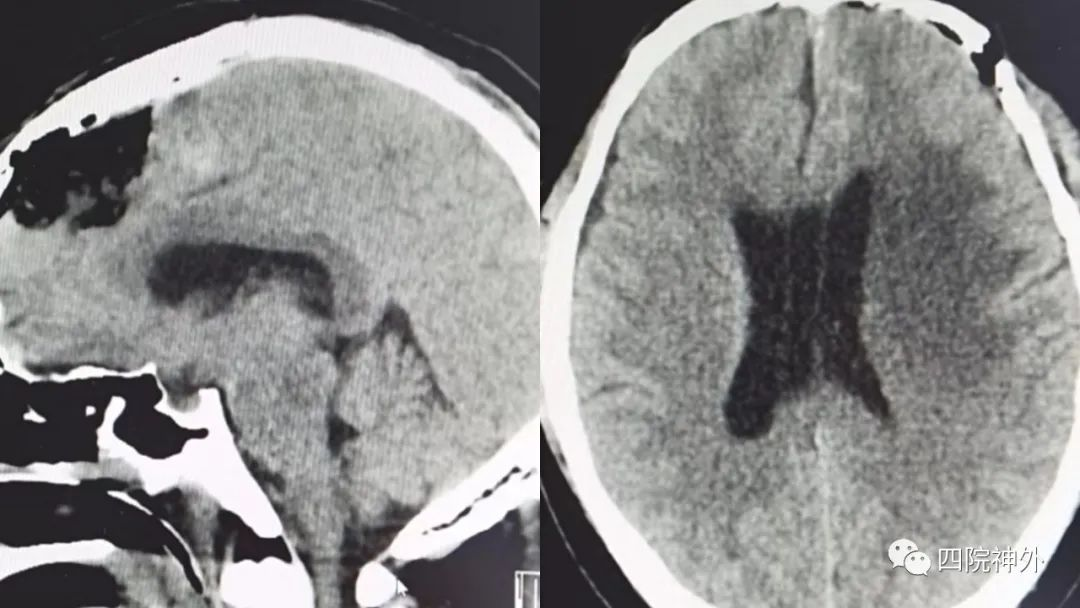

经过充分的手术风险评估及围手术期准备后,神经外科团队在全麻下为李先生行了“左额窦镰旁脑膜瘤显微切除术”,经过如履薄冰的操作,术中成功切除10cmx6cmx5cm的巨大脑膜瘤,术后CT提示肿瘤完全切除,术后李先生无肢体活动异常和感觉障碍,视力也慢慢的恢复,李先生及家人悬着的心也终于放下,现李先生已康复出院。

术后CT示肿瘤完全切除